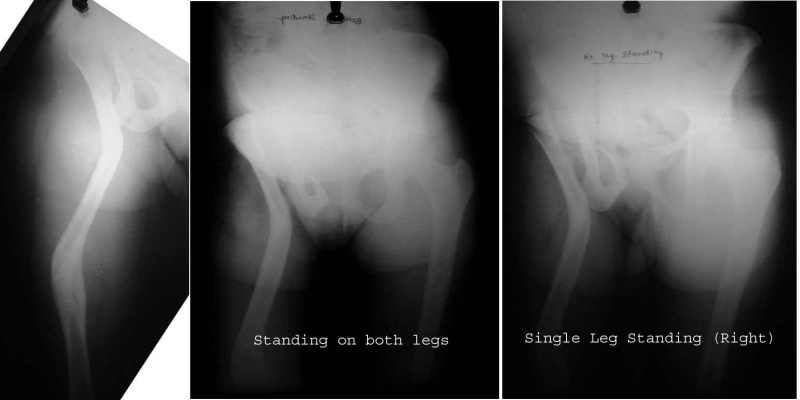

Certainly, this is an option and a valuable one, to restore limb length and reduce the trendelenburg gait for conditions like old septic arthritis of the hip, dislocated hips.

This operation - the Ilizarov Hip Reconstruction consists of an extreme valgus osteotomy in the proximal femur, to stabilise the unstable hip, a lengthening distally to equalise the limb lengths, and a varusization thru that lengthening zone to bring back the distal limb parallel to the other limb, and normalise the "mechanical axis".

Attached are some pics of a case of an 18 year old girl with shortening and trendelenburg lurch, both of which were corrected by the procedure.

The xrays in single stance show that the pelvis continues to remain level, in the single stance, despite the absence of the head.